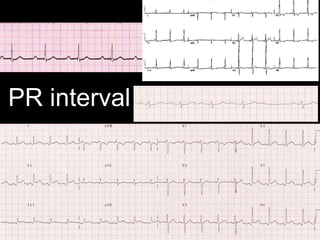

PR interval

• #17 1˚ HB eg rheumatic fever, short PR in Lown-Ganong-Levine syndrome, PR depression (and elevation in aVR) in pericarditis. Mobitz 1 = Wenckeback. TP segment is the baseline.